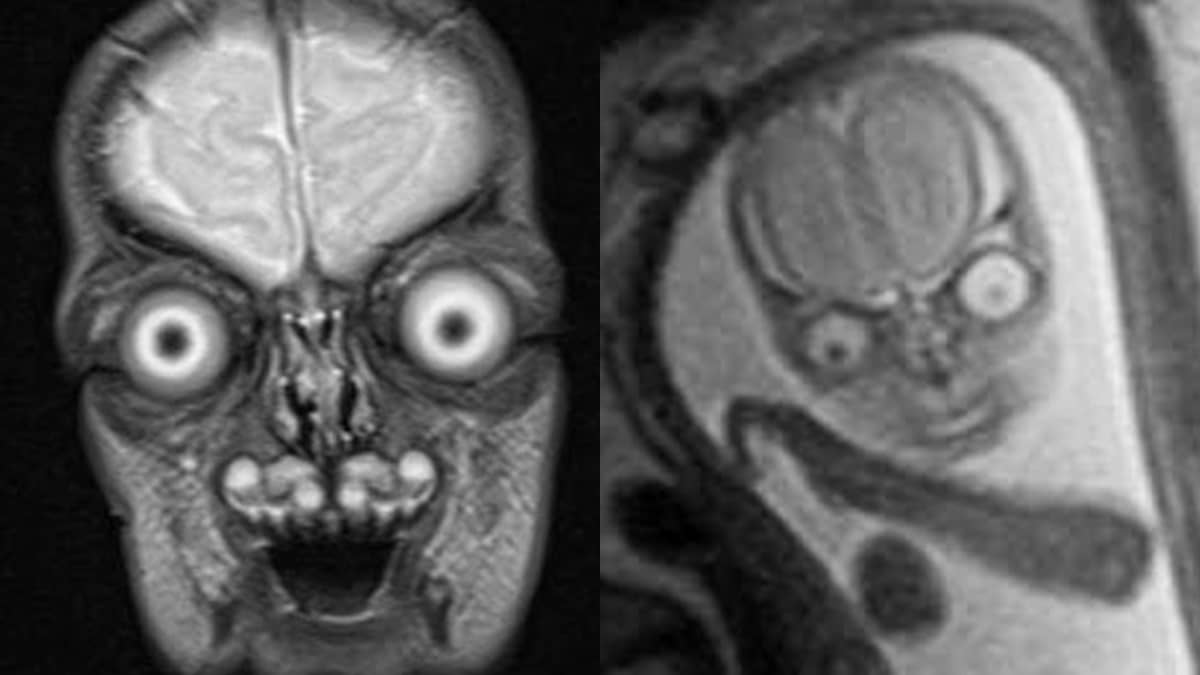

Babies seen through resonance imaging (MRI) r/oddlyterrifying

Babies seen through resonance imaging (MRI) r/oddlyterrifying Can Mri Hurt Baby To this date, there has been no scientific evidence demonstrating that mri is dangerous to the developing fetus. Mri is considered a very safe procedure. An mri can image the pregnancy and give healthcare providers a view of the placenta, baby’s brain, airway, lungs, and abdomen (commonly called the. Some studies have reported that having an mri in pregnancy is. Can Mri Hurt Baby.